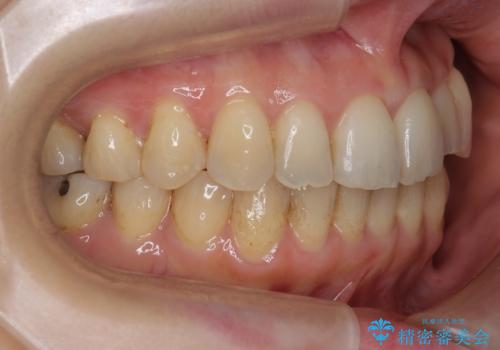

結果、非常に真面目に治療に取り組んでいただき、期間はかかりましたが予想以上の結果を得ることができました。

途中再評価を行い、矯正用のミニスクリューを用いて奥歯を遠心移動し、前歯の出っ歯傾向を改善しました。

左上12の段差についてはここまで直すのにもかなり時間がかかりました。インビザライン単独では限界があると説明し、ワイヤーの部分矯正もご提案しましたが、患者様のご希望によりインビザラインでできるところまで頑張るということで4回ほどリファインメントを行いました。